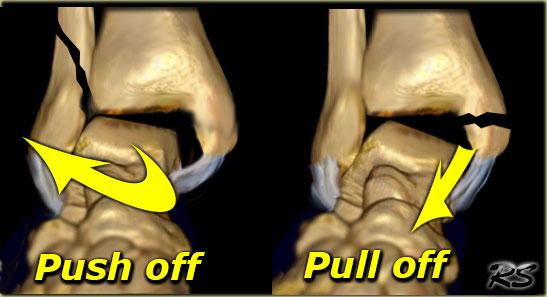

Gãy xương do lực kéo hoặc lực đẩy

Sự vững chắc của khớp

Khớp cổ chân có thể được hình dung như một vòng khép kín, trong đó cả xương lẫn dây chằng đều đóng vai trò quan trọng như nhau trong việc duy trì sự vững chắc của khớp.

Nếu vòng bị gãy ở một điểm, vòng vẫn còn vững chắc.

Khi vòng bị gãy ở hai điểm, vòng trở nên mất vững và có thể bị trật khớp.

Bất kỳ ai cũng có thể nhận ra rằng khớp cổ chân sẽ mất vững khi cả mắt cá trong lẫn mắt cá ngoài đều bị gãy.

Vấn đề trở nên phức tạp hơn khi có sự kết hợp giữa gãy xương và đứt dây chằng, vì tổn thương dây chằng không thể phát hiện được trên phim X-quang.